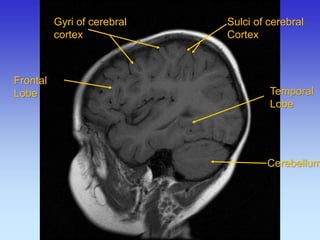

Gyri of cerebral cortex

Sulci of cerebral Cortex

Cerebellum

Frontal Lobe

Temporal

Lobe